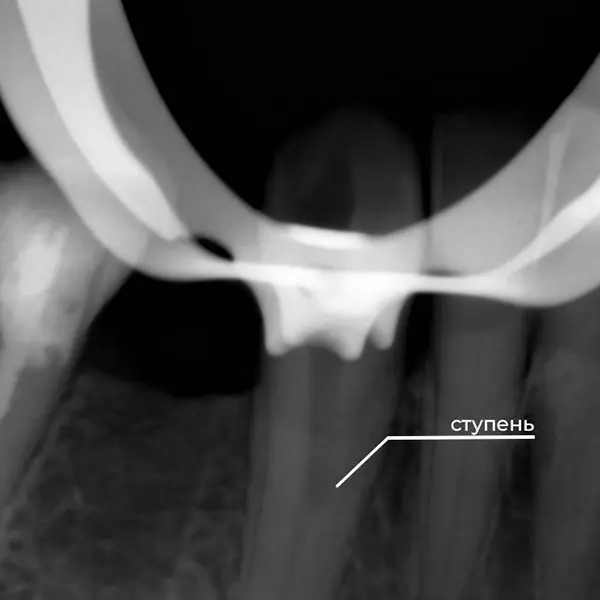

- Стоматологический порошок для ретроградного пломбирования: специальный порошок использовался для перекрытия сформированной “ступени” (изгиба или резкого изменения конусности), обеспечивая герметичность.